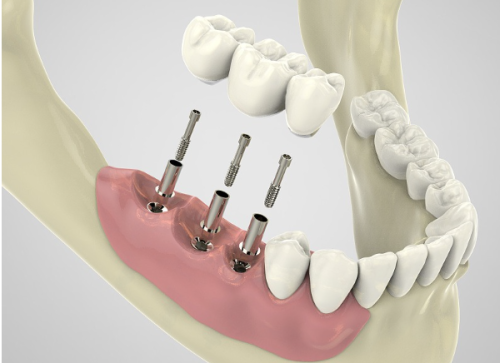

特别多人都在问西安双宝口腔医院怎么样,其实它不仅技术好,性价比也非常不错。在技术方面,医院的医生团队不断学习和掌握精良的口腔医疗技术,能够为患者提供个性化的治疗方案。比如在种植牙项目中,医生会根据患者的口腔情况、身体状况等因素,选择更适合的种植体和种植方案,确保种植成效和安心性。在性价比方面,2025价格表特别实惠,让患者花较少的钱就能享受到优质的口腔医疗服务。以种牙搭桥为例,价格为16800元起,相比一些大型口腔医院,价格优势明显。而且医院还经常推出一些优惠活动,进一步降低患者的治疗成本。

西安双宝口腔医院的设备齐全,拥有精良的口腔检查设备、治疗设备等。这些设备能够帮助医生更正确地诊断病情,制定更科学的治疗方案。例如,口腔CT设备可以清晰地显示牙齿和颌骨的内部结构,为种植牙、正畸等治疗提供重要的依据。在服务方面,医院始终坚持以患者为中 心,从患者进门的那一刻起,就有专精的导医为患者提供引导和帮助。在治疗过程中,医生和护士会耐心地解答患者的疑问,关心患者的感受,让患者在舒适的环境中接受治疗。治疗结束后,医院还会为患者提供详细的护理指导和回访服务,确保患者的口腔健康得到持续关注。